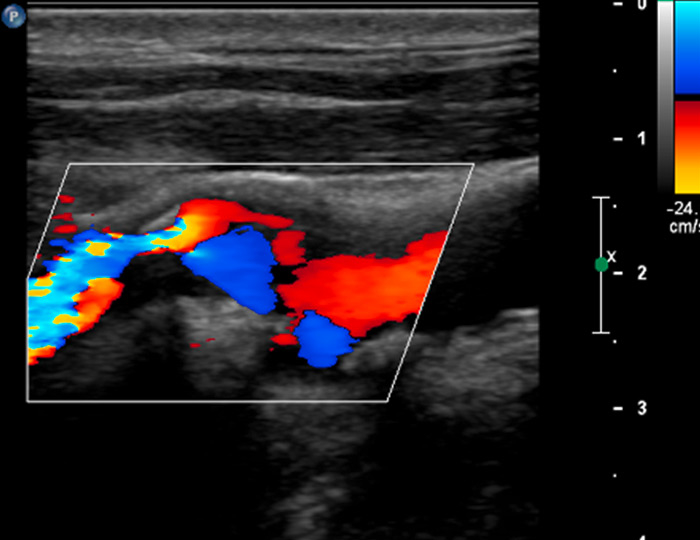

Figure 1

A 58-year-old patient with myocardial infarction 2 months previously with hypoechogenic plaque at the origin of the left internal carotid artery on B-mode ultrasound (A). Extensive intraplaque neovascularisation (arrows) on CEUS imaging (B).

Figure 2

A 61-year-old patient with asymptomatic high-grade stenosis at the origin of the left internal carotid artery on colour Doppler ultrasound (A). Moderate intraplaque neovascularisation within the carotid stenosis at the near wall on CEUS imaging (arrows) and no neovascularisation at the far wall (B).

In our own clinical study, we analysed 293 atherosclerotic lesions with standard and CEUS imaging [29]. The degree of intraplaque neovascularisation was graded visually as no, moderate or extensive enhancement. Similar to other investigators we found that predominantly hypoechoic carotid plaques on B-mode ultrasound, known to be associated with an increased risk of cardiovascular events significantly more often, had a higher grade of intraplaque neovascularisation on CEUS (fig. 1). In accordance with the concept that more vulnerable atherosclerotic lesions had a higher degree of neovascularisation, we found also that intraplaque neovascularisation on CEUS correlated well with lesion severity based on the degree of stenosis and plaque thickness (fig. 2).